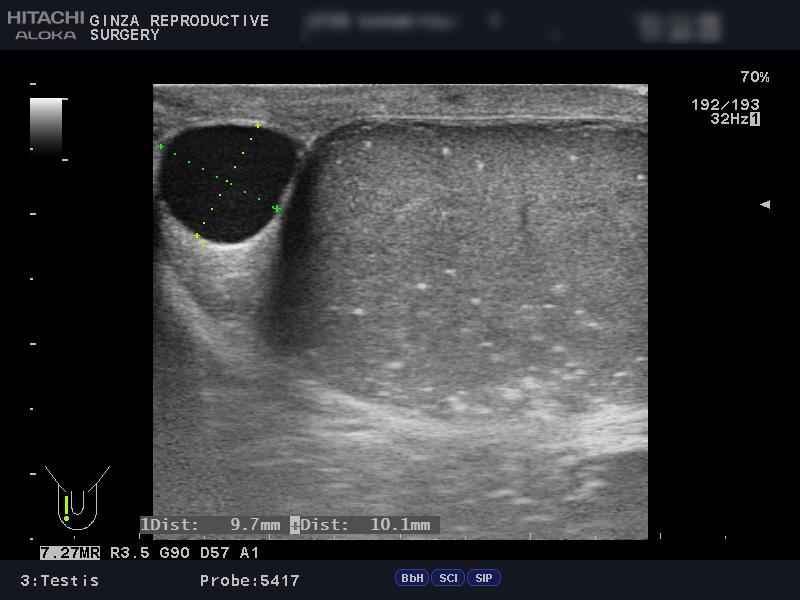

次は、別の患者さんのエコー画像で、左右の精巣を比較してみましょう。

精巣の大きさに左右差があることがわかります。精巣の大きさは左16ml・右20mlで、精索静脈瘤により左側が萎縮しています。

左右の精巣に多数見える白い点は、精巣機能低下により石灰化してきている部分です。石灰化は、男性不妊との関連が示唆されていますが、はっきりとした原因はわかっていません。

右側の精巣には9.7mm×10.1mmの精液瘤も見られます。精液瘤治療の手術は精巣機能低下につながることがあり、不妊治療中の場合は経過観察にとどめます。